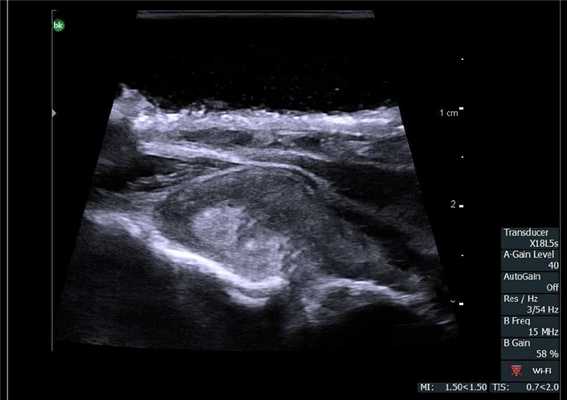

Органосохраняющие операции при образованиях почек должны сочетать в себе минимальный объем для сохранения функции почек и онкологические принципы лечения. Для определения объема вмешательства во всем мире активно используют ИУОЗИ не только при открытых и лапараскопических, но и роботических операциях [30, 31]. Оценивают не только объем поражения ткани почки, но и распространение на почечные сосуды, а также нижнюю полую вену [32].

Опухоль почки. Сканирование интраоперационным роботическим датчиком 8826